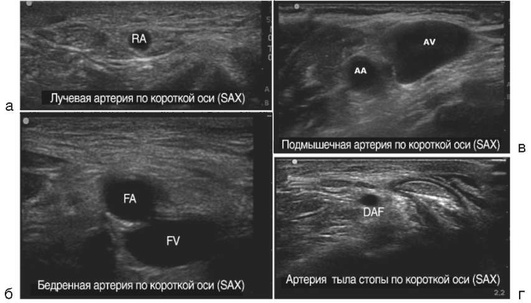

Катетеризация центральных вен

Показания к установке центрального венозного катетера (ЦВК).

1. Потребность во введении инфузионных сред или лекарственных препаратов при невозможности обеспечения требуемого объема, скорости, эффективности и безопасности инфузионной и/или медикаментозной терапии за счет катетеризации периферических вен и/или внутрикостного введения.

ОСНОВНЫЕ ПОЛОЖЕНИЯ Выбор доступа

В соответствии с приказом Минздрава России от 23.07.2010 №541н «Об утверждении единого квалификационного справочника должностей руководителей, специалистов и служащих», врач анестезиолог-реаниматолог определяет показания и производит катетеризацию центральных вен. При выборе внутривенного доступа, типа катетера и количества просветов в нем врач, устанавливающий ЦВК, учитывает характер заболевания, анатомическую область места доступа, длительность и интенсивность терапии, риски осложнений, включая инфекционные и иные индивидуальные особенности пациента.